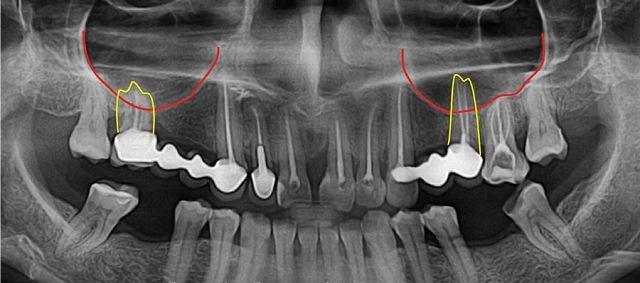

Из верхнего ряда зубов наиболее близко к гайморовой пазухе расположены зуб мудрости и крупные коренные зубы.

Причинами возникновения перфорации могут быть длинные корни зубов, а также индивидуальные особенности строения костной ткани, относящейся к лицевому отделу черепа.

Обострения могут быть вызваны эндодонтическим лечением. При удалении зуба корень может задевать пазуху, что приводит к повторной перфорации дна гайморовой пазухи.

При эндодонтическом лечении зубов мудрости стоматологу необходимо осторожно работать с корнем зуба, находящимся в гайморовой пазухе, чтобы избежать повреждения синуса.

Верхний ряд зубов отделен от гайморовых пазух тонкой костной пластиной, толщина которой в некоторых местах может составлять всего один миллиметр. Поэтому причинить повреждение в этой области довольно легко.